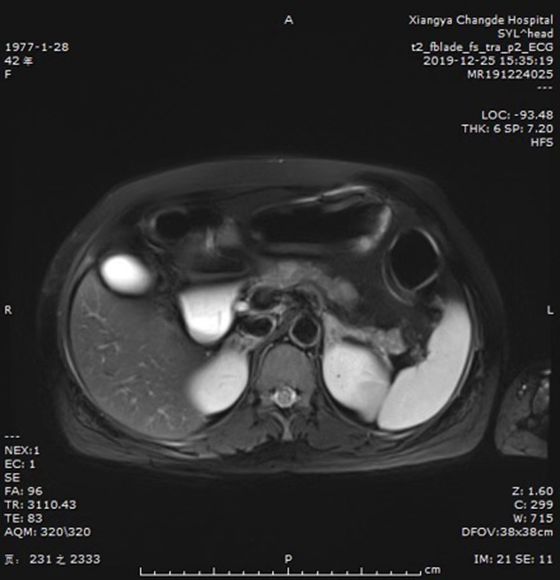

磁共振显示患者胰腺体尾部有多发结节

经反复病史询问梳理及CT、MRI和抽血检验,所有线索指向胰腺神经内分泌肿瘤(pNENs)。经普外科和内分泌科会诊,该病为功能性的pNENs,手术治疗是目前最佳的治疗方案。

普外科主任肖广发阅片后发现患者胰体尾部有多个1.0-2.0cm大小结节,影像及症状均符合胰岛素瘤(pNENs的一种),一系列检查后又意外发现黄女士合并甲状旁腺肿瘤、左侧肾上腺腺体增厚,可能为多发性内分泌腺瘤病,而当务之急是解决患者的低血糖症状,避免继续神经系统损伤。